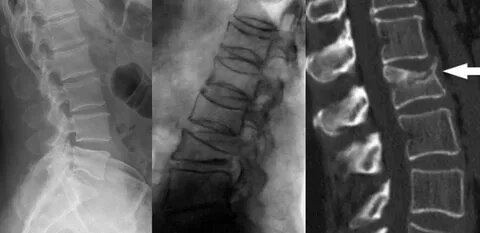

Остеопороз развивается когда разрушение костной ткани происходит быстрее, чем ее восстановление. С возрастом этот процесс ускоряется, особенно у женщин после менопаузы. Кальций вымывается, кости становятся пористыми и хрупкими как старый мел.

Обычно к 70 годам человек теряет до 30% костной массы. Но в северных регионах России, включая Якутию, ситуация складывается иначе благодаря особенностям образа жизни местного населения.